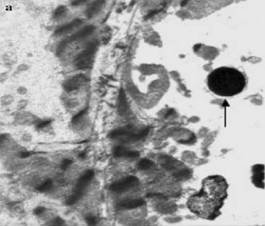

Ультраструктура кардиомиоцита левого желудочка крысы после воздействия ИЗП (Погодина и соавторы, 2006)

Электронномикроскопическое исследование Погодиной Л.С. и соавторов кардиомиоцитов левого желудочка крыс в периферических зонах очагов некроза показало значительную гетерогенность ультраструктуры кардиомиоцитов (различия в форме и структуре ядер, митохондрий, сократительного аппарата). Все кардиомиоциты были разделены на три типа (прежде всего основываясь на различиях в строении ядер): A (овальные ядра с довольно ровной поверхностью и небольшими ядрышками), B (ядра с многочисленными инвагинациями ядерной оболочки, увеличение конденсации хроматина по всему объёму ядра, крупные ядрышки), С (инвагинация ядерной оболочки и конденсация хроматина сильно выражены, ядрышки меньше, чем в контроле) [6].

Митохондрии играют ключевую роль на начальных стадиях развития апоптоза, поэтому изменения в их структуре является важным морфологическим критерием апоптоза кардиомиоцитов. В работе Погодиной Л.С. и соавторов отмечалось просветление матрикса митохондрий с редукцией крист (наиболее выраженное у кардиомиоцитов С типа), также вытеснение митохондрий из центральных участков клетки на периферию, где они скапливались в многочисленных выступах саркоплазмы («почках») [6].